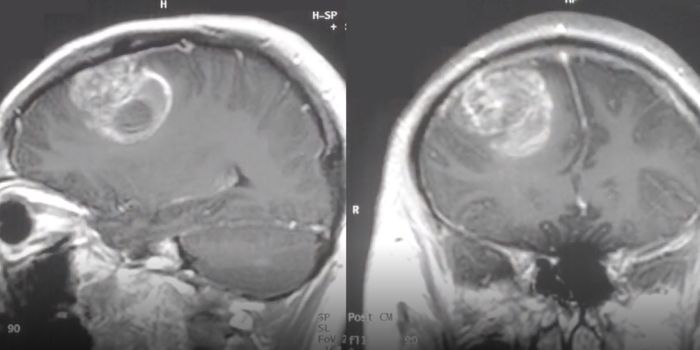

SEP 14, 2020Genetics & GenomicsWhile they may occur in adults, a rare, aggressive type of brain cancer called atypical teratoid rhabdoid tumors tend to ...